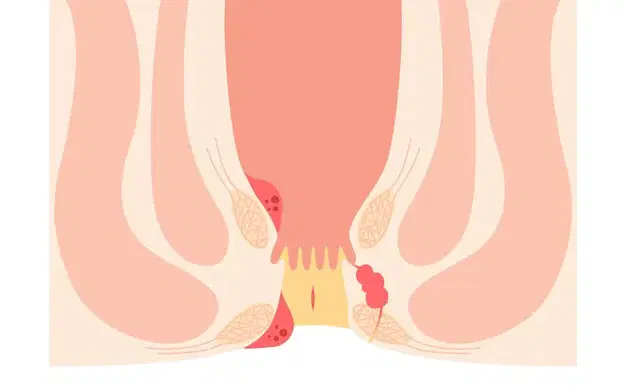

Piles Treatment in Vijayawada

At Vijayawada Gastro Centre, we provide advanced and minimally invasive treatment for piles, offering personalized care for fast and effective relief. Piles are swollen veins in the anal or rectal region, causing pain, bleeding, itching, and discomfort. Our experts use modern diagnostic tools such as anoscopy and colonoscopy to ensure accurate evaluation. Treatment options include lifestyle changes, medications, rubber band ligation, sclerotherapy, infrared coagulation, and advanced laser therapy. Laser treatment offers minimal pain, quick recovery, and same-day discharge. Our specialists ensure compassionate, safe, and tailored care for every patient.

Anal Fistula Treatment in Vijayawada

At Vijayawada Gastro Centre, we offer specialized care for anal fistula using advanced diagnostic and minimally invasive treatment methods. An anal fistula is an abnormal tunnel near the anus that can cause pain, swelling, and discharge if untreated. Our experts use clinical examination, MRI fistulogram, and endoanal ultrasound for accurate diagnosis. Treatment options include laser fistula surgery, fistulotomy, seton placement, and the LIFT procedure for complex cases. With experienced gastroenterologists, state-of-the-art facilities, and personalized care, we ensure safe, effective, and faster recovery for every patient.

Fissure Treatment in Vijayawada

Fissures are small tears in the lining of the anal canal that cause sharp pain, bleeding, and discomfort during bowel movements. At Vijayawada Gastro Centre, our specialists provide advanced and effective fissure treatment with a focus on quick relief and long-term healing. We use modern diagnostic methods and offer both conservative and minimally invasive options, including medications, lifestyle guidance, Botox therapy, and laser treatment for persistent cases. Our personalized approach ensures reduced pain, faster recovery, and prevention of recurrence. With expert care and state-of-the-art facilities, we deliver safe and compassionate fissure treatment in Vijayawada.